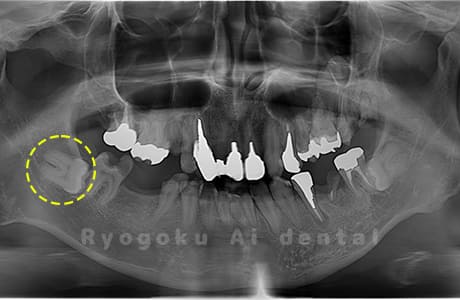

Case01

- 原因

- 水平埋伏智歯

- 治療内容

- 下顎の水平埋伏智歯を抜歯

<リスク・副作用>

手術後は痛み、腫れ、痺れなどの副作用が生じる場合があります。